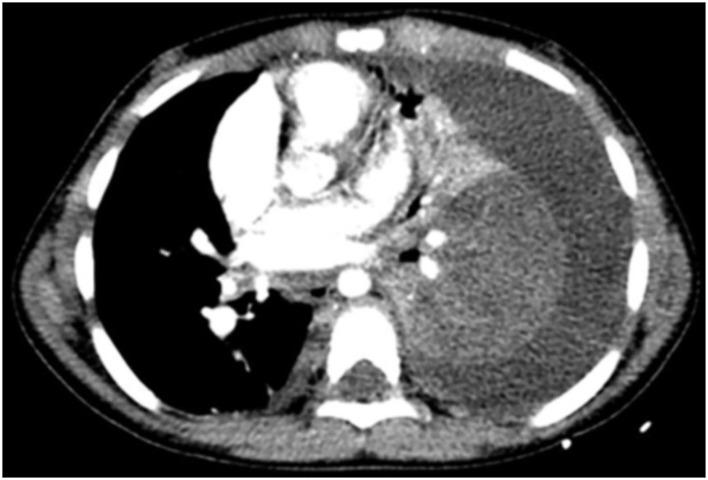

儿童坏死性肺炎:胸部计算机断层扫描与肺部超声检查的对比

The utilization of contrast-enhanced computed tomography (CT) of the chest for the diagnosis of necrotizing pneumonia (NP), a complication of community-acquired pneumonia, is controversial because of the inherent ionizing radiation involved. Over the past few years, the growing availability of bedside Lung Ultrasound (LUS) devices has led to increased use of this nonionizing imaging method for diagnosing thoracic pathology, including pneumonia.

OBJECTIVE

The objectives of this study were as follows: first, to compare the performance of LUS vs. CT in the identification of certain radiological signs of NP, and second, to determine whether LUS could replace CT in the diagnosis of NP.

Pleural effusions were demonstrated almost systematically (100% on CT vs. 95.8% on LUS). Visualization of septations in pleural effusions was clearly superior on LUS (20.4% on CT vs 62.5% on LUS). Concerning the detection of necrosis, we observed a strong correlation between LUS and the gold-standard CT (95.8% on LUS vs. 93.7% on CT). Parenchymal cavities were more easily detected on CT than on LUS (79.1 vs. 35.4%).

CONCLUSION

LUS has shown to be as effective as CT in the diagnosis of NP. The use of CT in patients with NP could be limited to the detection of complications such as bronchopleural fistulae in unfavorably evolving diseases.